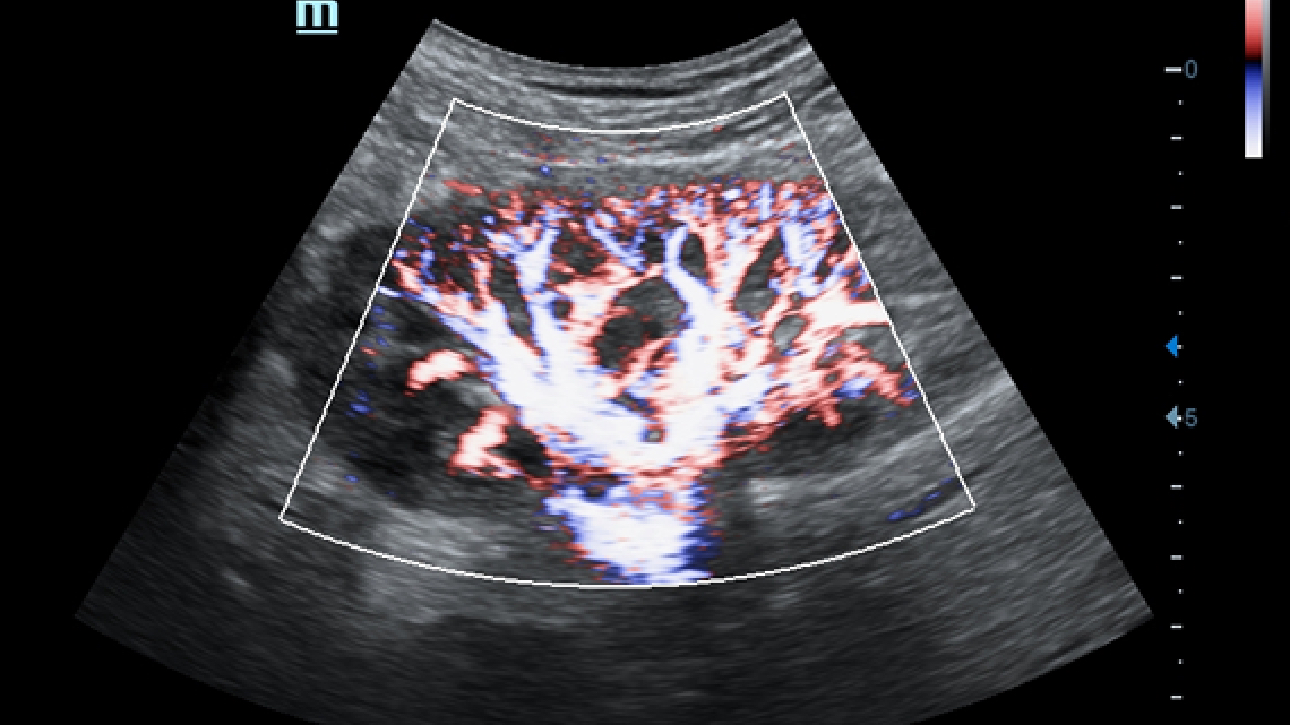

Klinische Bilder